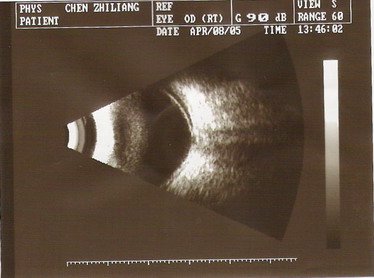

2005年4月8日因视物不清来诊,查体:VOD:0.25,VOS:1.0,右眼瞳孔直径5.0mm(对侧3.0mm),光反应迟钝,周边前房3/4CT,眼底视乳头色正,血管偏位,C/D=0.6,眼底鼻侧视网膜略显平脱。眼压:右25.3mmHg,左17.0mmHg,B超提示右眼视网膜脱离,视盘凹陷(青光眼型)。

2005年4月8日B超:右眼玻璃体轻度混浊,右眼视网膜脱离,视盘凹陷(青光眼型)